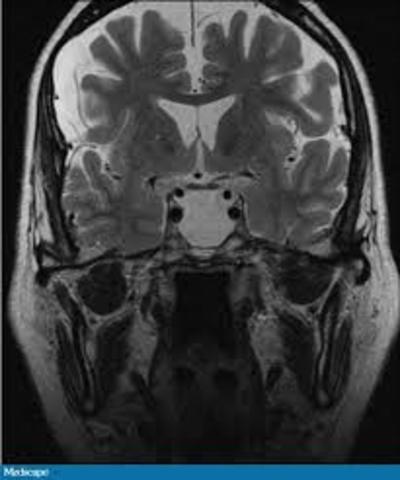

• Teoría panhipopituitario de la anorexia

Teoría panhipopituitario de la anorexia

Aparece la teoría del origen panhipopituitario de la anorexia, pero más tarde se desmontó tal teoría.